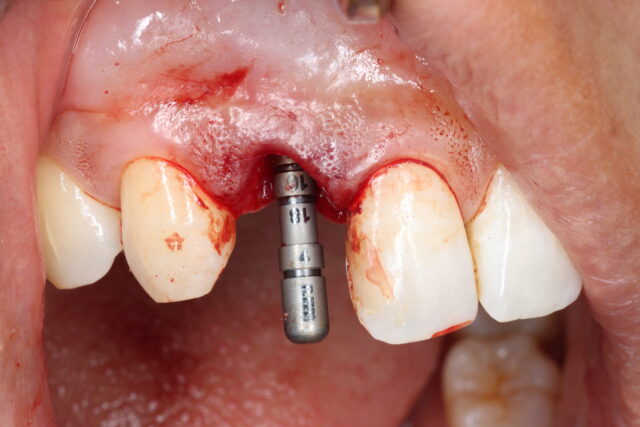

症状 上顎右側側切歯のう蝕、歯根破折による変色 年齢・性別 20代女性 治療期間 4か月 治療方法 上顎右側側切歯がコンポジットレジンの二次カリエスのため歯根内までう蝕が広がっており、審美障害と歯根の破折をきたしており、予後不良と判断した。 抜歯を行ったと同時にBLTインプラント埋入を行い、骨増生と軟組織の移植を行った。 上部はジルコニアクラウンをスクリュー固定した。 費用 55万円 デメリット・注意点 保険適応外治療。 骨増生、軟組織移植を必要とする。 -